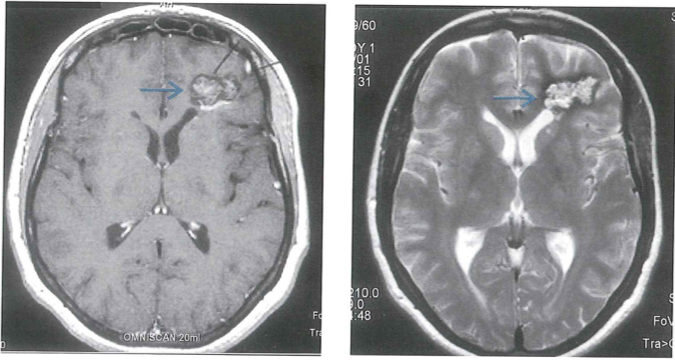

Εικόνα 1. Σηραγγώδες αιμαγγείωμα αριστερού μετωπιαίου λοβού το οποίο υπέστη ρήξη και προκάλεσε αιμορραγία. Επισημαίνεται με γαλάζιο βέλος σε μαγνητική τομογραφία, σε εγκάρσια τομή Τ1 (α) και εγκάρσια τομή Τ2 (β).